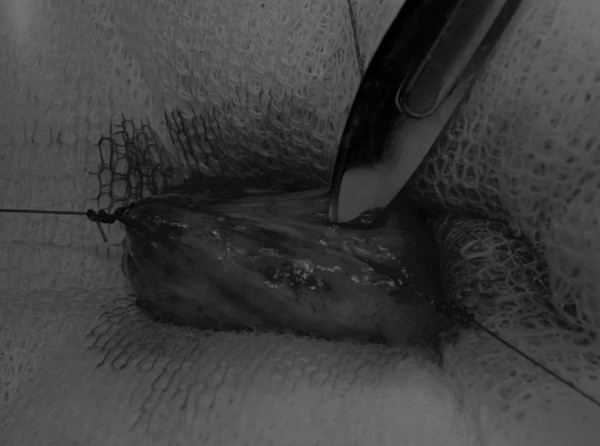

在牵引缝线之间选择血管扩张较差的区域用手术刀切开膀胱壁(图3)。在牵引缝合线之间用手术刀在血管不良的区域做切口。切开膀胱壁后,膀胱内的手术可按手术方案实施,例如取出结石(图4)。

图3 避开主要的膀胱血管,做一个尽可能小的切口